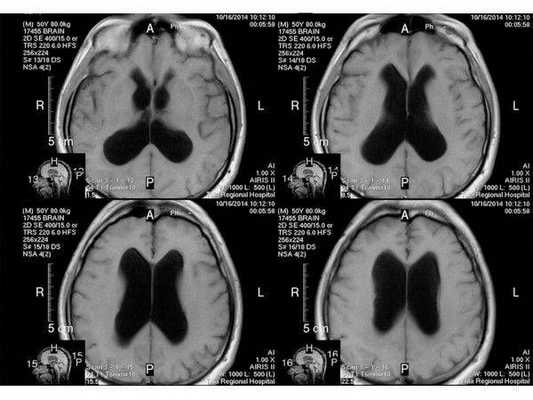

МР-томограмма нормального головного мозга. Серым цветом изображено вещество мозга, белым - ликвор. Нормальная величина жидкостных пространств головного мозга (они щелевидны). Желудочки видны внутри мозга. Субарахноидальные пространства - белая кайма вокруг мозга.

МР-томограммы при внутричерепной гипертензии и гидроцефалии. Результат недостаточного лечения повышенного внутричерепного давления. Видно избыточное скопление ликвора внутри головного мозга (в виде бабочки) и снаружи мозга (широкая белая кайма). Объем мозгового вещества уменьшен - атрофия головного мозга от давления жидкостью.

- Расширение жидкостных полостей головного мозга и разрежение мозгового вещества по краю желудочков мозга, ясно видимое при компьютерной рентгеновской томографии (КТ) или магнитно-резонансной томографии (МРТ);